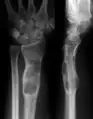

X-ray showing calcified enchondromas localized in finger a 37-year-old patient affected with Ollier disease